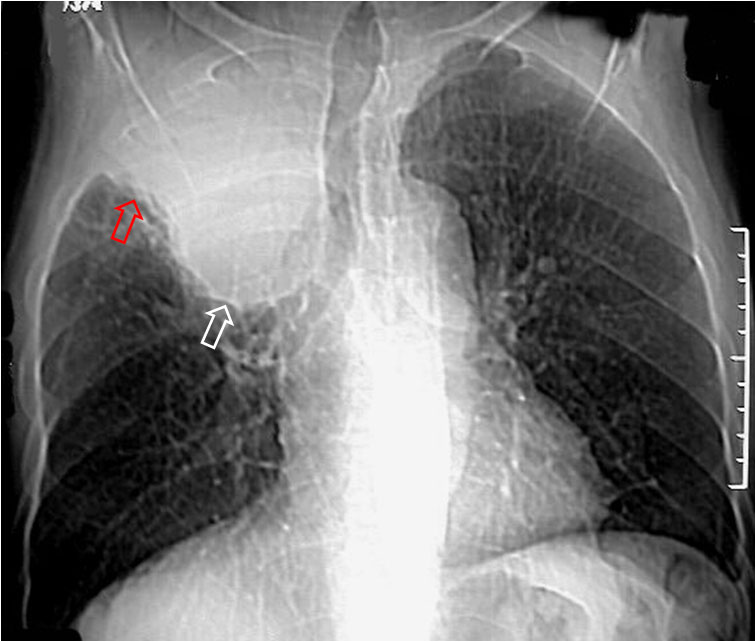

Imagen en forma de «S» itálica que forma el margen cóncavo del lóbulo superior derecho colapsado (flecha roja) y el margen convexo de una masa hiliar derecha (flecha blanca) causante del colapso. En el colapso de otros lóbulos hay imágenes equivalentes a la «S» de Golden, pero no tan gráficas.

En la fotografía, tumor epidermoide hiliar derecho.